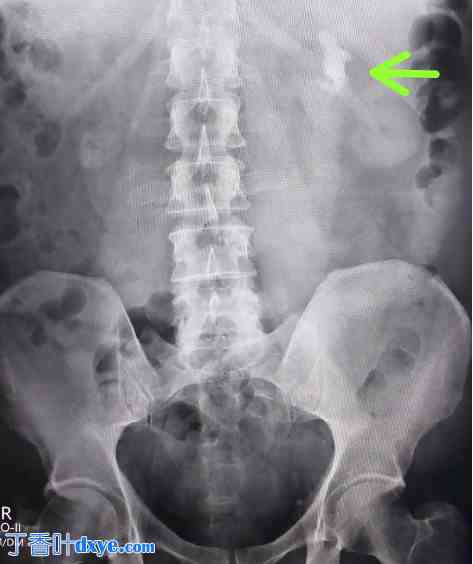

图3

术前X光片显示左肾结石。

一名63岁男性,无已知合并症,因左侧腰痛及下尿路症状六个月就诊。放射学检查显示左肾结石(如图1、2和3所示),提示需要进行经皮肾镜取石术(PCNL)。患者接受了经皮肾镜取石术(PCNL),并置入DJ支架用于术后引流(如图4所示)。此外,还置入了肾造瘘管用于引流。